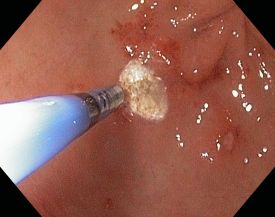

- Abtragung von Polypen im oberen Verdauungstrakt

- Abtragung von Polypen im unteren Verdauungstrakt

Bei Bedarf können außerdem über einen Instrumentierkanal im Koloskop Gewebeproben (Biopsien) entnommen werden oder therapeutische Maßnahmen, wie Entfernung vom Darmpolypen, durchgeführt werden.

Im Rahmen von endoskopischen Untersuchung lassen sich häufig Blutungsquellen im Magen oder Darm aufspüren. Eingespritzte blutstillende Substanzen verhelfen in vielen Fällen zum Stillstand, so dass nicht operiert werden muss.